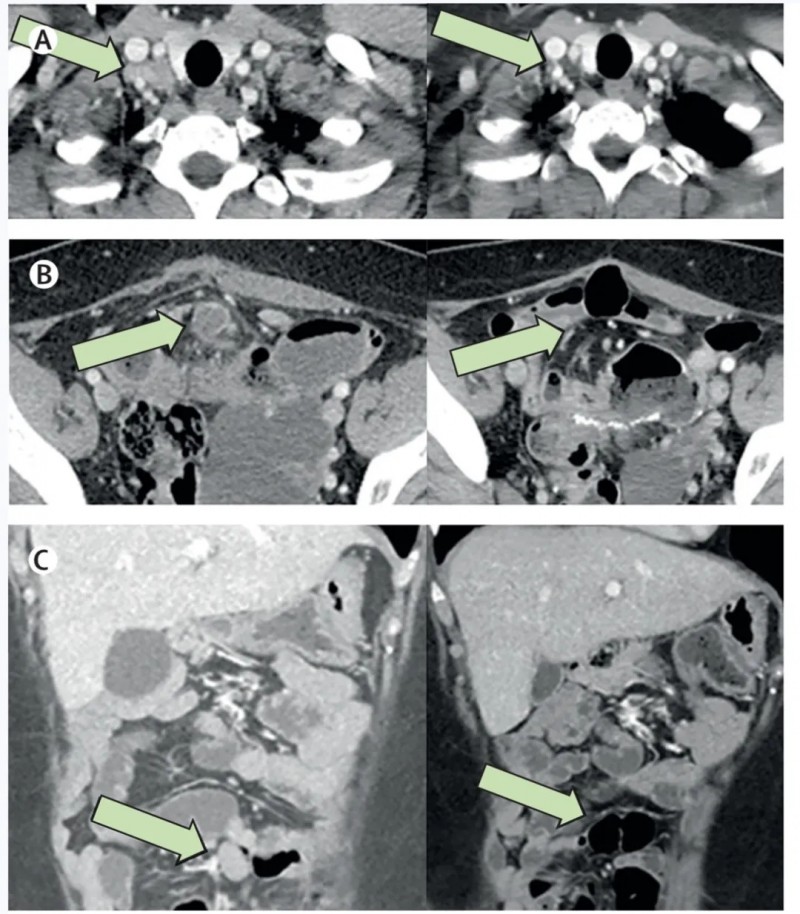

尤为值得关注的是一例晚期肺腺癌患者:该患者合并淋巴结、胸膜及骨转移,经放疗+靶向治疗后病情仍持续进展,随后入组接受GC101 TIL细胞回输治疗。

结果令人振奋:在回输后第6周、12周、18周、24周的定期肿瘤影像学评估中,疗效持续显现——第二次增强CT即显示靶病灶缩小36%,最终达到部分缓解(PR);更为惊喜的是,回输24周内,患者未接受其他任何治疗,肿瘤病灶仍在持续缩小,展现出持久的抗癌效果!

▼该患者在接受GC101 TIL细胞回输治疗前,以及治疗6周、12周、18周、24周的CT对比图

▲图源“JUNCELL”,版权归原作者所有,如无意中侵犯了知识产权,请联系我们删除